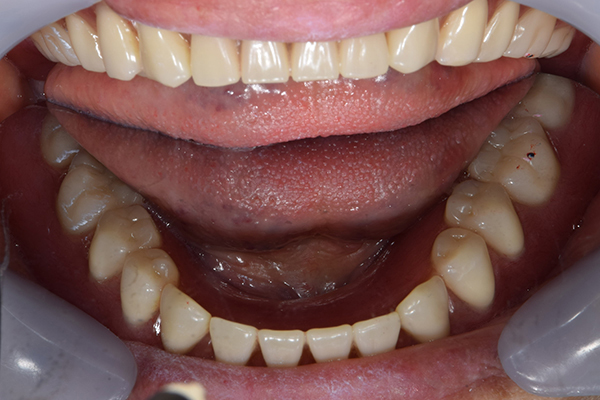

完成した入れ歯とかぶせ物です。 入れ歯への寛容度が高い患者様でしたので、 金属は使用せず、プラスチックのみで上は仕上げました。 下顎も歯は1本減ってしまいましたが、しっかり 入れ歯が維持できる様な構造にしました。

お口の中に入れた状態です。 見た目も最初とほとんど変わることなく作成できました。 維持や吸着に関しても問題ないようでした。